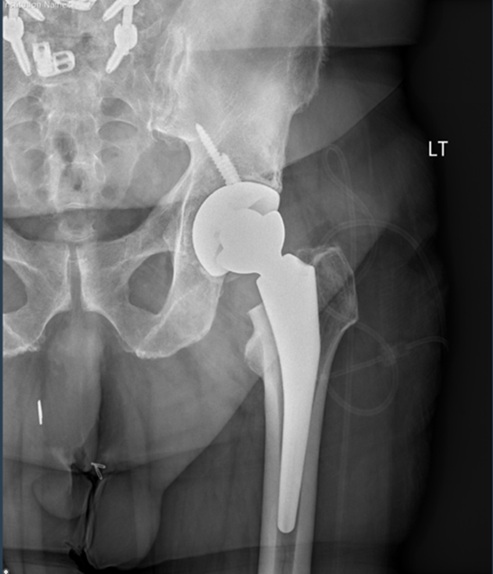

Figure 8, 9 and 10. AP pelvis, AP of the left hip, and lateral of the left hip demonstrating left reverse total hip arthroplasty without acute complication.

Post-op Radiographs

Figure 8.

Figure 9.

Figure 10.